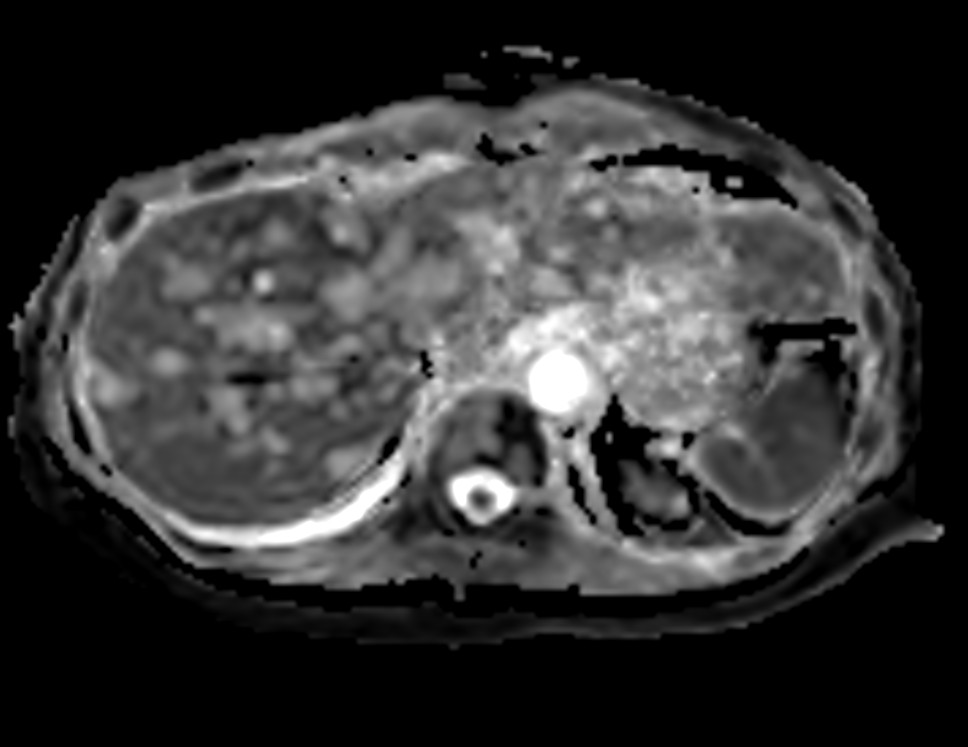

Axial DWI b200

Axial DWI b800

Axial DWI ADC